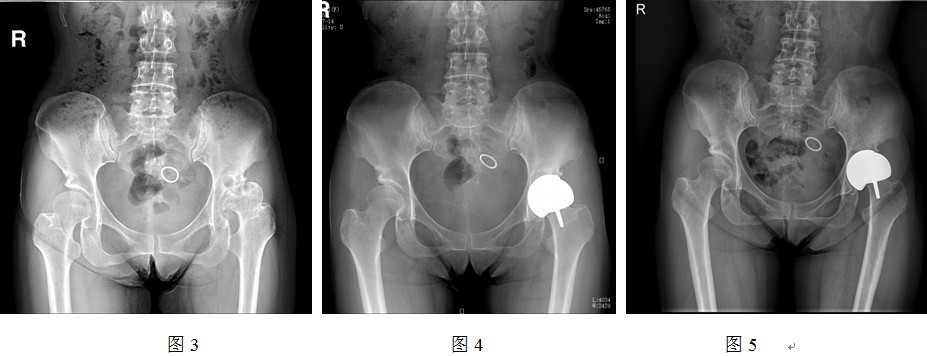

随访复查影像学评价由三位高年资主治医师分别独立阅片测量,取平均值。术前髋臼角(Sharp角)33.8~56.4度(平均47.7±6.5度),头颈比例1.29~1.64(平均1.47±0.11),颈干角126.7~162.2度(平均141.2±9.7度),CE角-7.5~28.8度(平均12.3±12.3度);术后臼杯外展角22.4~69.3度(平均46.8±12.9度),假体柄干角126.8~159.1度(平均143.0±9.2度);髋臼假体完全被骨床覆盖6髋,外上缘外露小于0.5cm的 2髋,外上缘外露超过0.5cm的5髋。1例患者于术后2年复查时摄片发现髋臼松动,臼杯边缘骨质出现透亮带,且臼杯外展角由原来的69度变化为71度(详见图3~5),但患者无明显临床不适。其余各例影像学检查随访未见关节脱位、骨折、松动、异位骨化等现象。

DDH患者的髋臼较浅,直径变大,平均髋臼Sharp角大于45度,髋臼外上缘骨质覆盖不足,在放置髋臼假体的时候就存在如下矛盾:如果将假体臼杯外展角放置为45度以下(小于Sharp角),虽然可以增加股骨头假体和髋臼假体的接触面积,但是假体边缘则外露过多,无法达到骨覆盖75%的要求,影响髋臼稳定性;如果为减少臼杯外上缘外露而将外展角放置在45度以上,虽可使骨性覆盖达到75%的标准,但同时减少股骨头假体和臼杯假体的接触面积,负重关键区域的面积减少,髋臼假体外上缘条带应力集中,磨损加快,松动风险同样会增加。从本研究的结果就可以验证这一现象。本组中某患者左髋为Karl III度发育不良(图3~5),术中角度、方向定位难度较大,虽然达到了较多的假体骨性覆盖,但使得术后髋臼外展角远远超过45度,造成髋臼顶部应力集中,为术后假体松动埋下了隐患。

患者毕××,女,54岁,因“反复左髋部疼痛5年余,加重伴跛行半年”于2008年3月27日入院。术前骨盆正位(图3)显示双侧髋关节发育不良,Karl Perner分类右侧II度、左侧III度。术前Harris评分62分,2008年3月31日行左侧髋关节表面置换术(Depuy ASR系统),因畸形较重,影响术中判断假体放置位置,导致髋臼外展角度放置为69度(图4),出院时Harris评分90分。术后2年随访Harris评分91分,患者虽无临床不适症状,但复查骨盆X线发现髋臼松动(图5),臼杯边缘透亮线产生,此时髋臼外展角变化为71度。